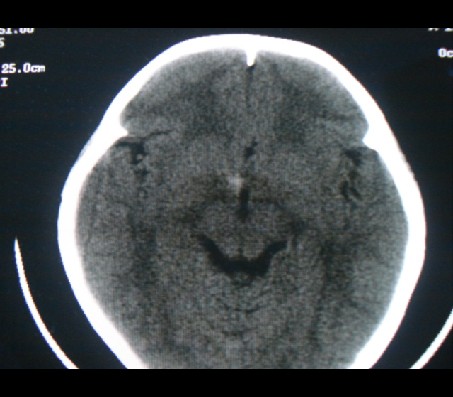

男性,12岁。反复头痛呕吐半月。脑积液无异常。病变部位ct值32hu,dwi无异常。

平扫看首先考虑颅咽管瘤,病人需增强扫描。

鞍内囊性占位性病变,t1wi、t2wi,均为高信号影。ct平扫为等密度。发病年龄较小。故首先考虑颅咽管瘤,可以做ct增强扫描

符合鞍上及鞍内颅咽管瘤影像表现,